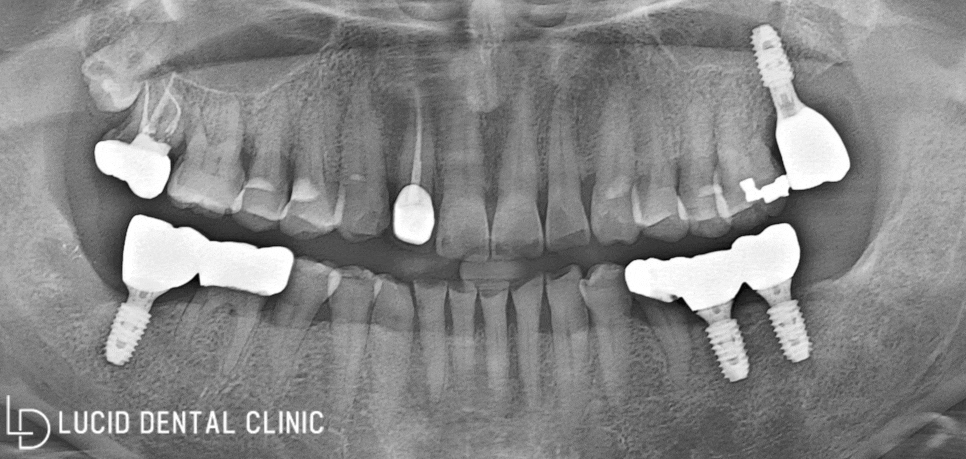

- 임플란트 수술 종료

픽스처 식립 후 약 4개월이 지나,

제작한 보철을 체결하였는데요

위와 같이 임플란트 수술 을

무사히 종료하였습니다! ㅎㅎ

초진과 달리, 튼튼한 교합 및 저작 기능과

심미적인 기능을 모두 되찾아 드렸습니다.